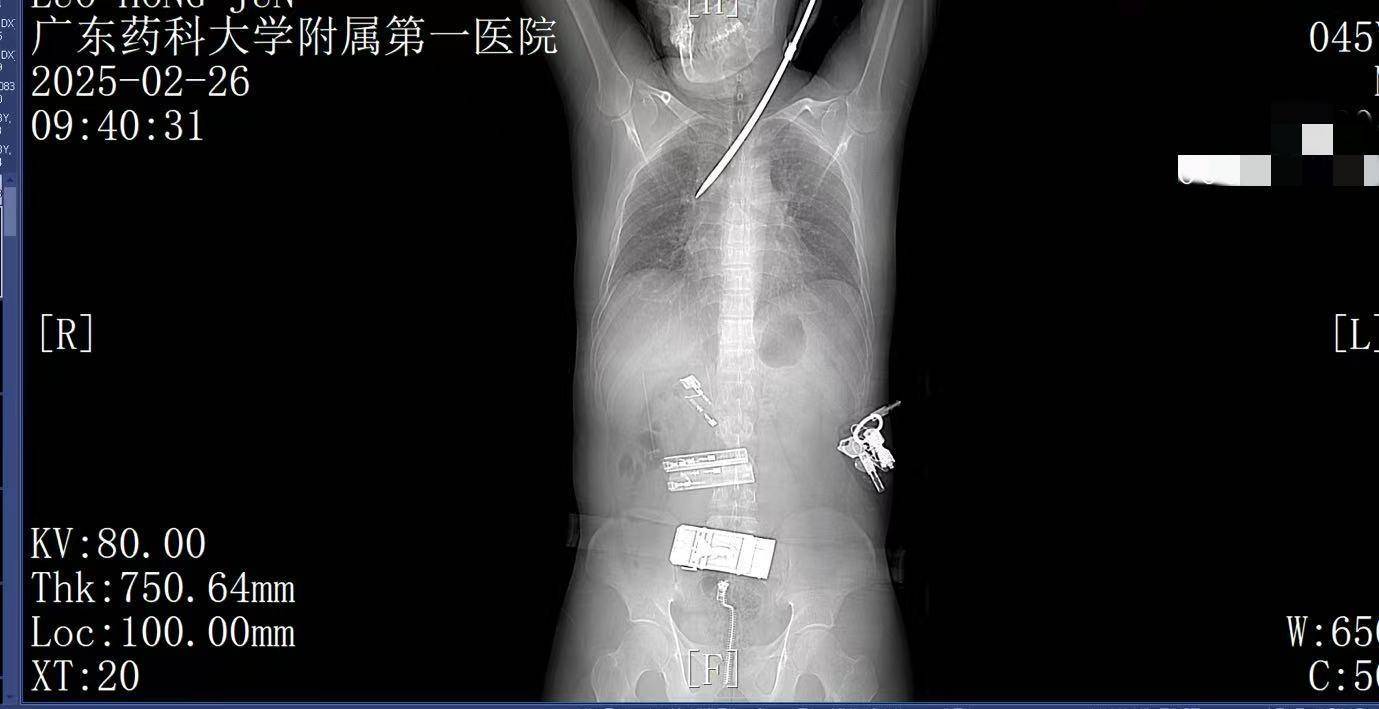

9:39,救护车到达医院大门,院内急救团队已经做好准备炒币秘籍。在紧密监护的情况下,全程采用绿色通道。到达医院时,罗师傅已经面色苍白,呼吸急促。螺丝刀已深深刺入罗师傅右肺,随时可能因大出血而危及生命。

9:41,快速完成头+胸+腹部CT检查,经多学科会诊,明确螺丝刀异物刺入肺部炒币秘籍。CT显示螺丝刀紧贴肋间血管、上肺后段动脉,尖端距右肺门仅2厘米,一旦贸然拔出螺丝刀,极有可能引发大出血,导致失血性休克甚至死亡,必须紧急手术。